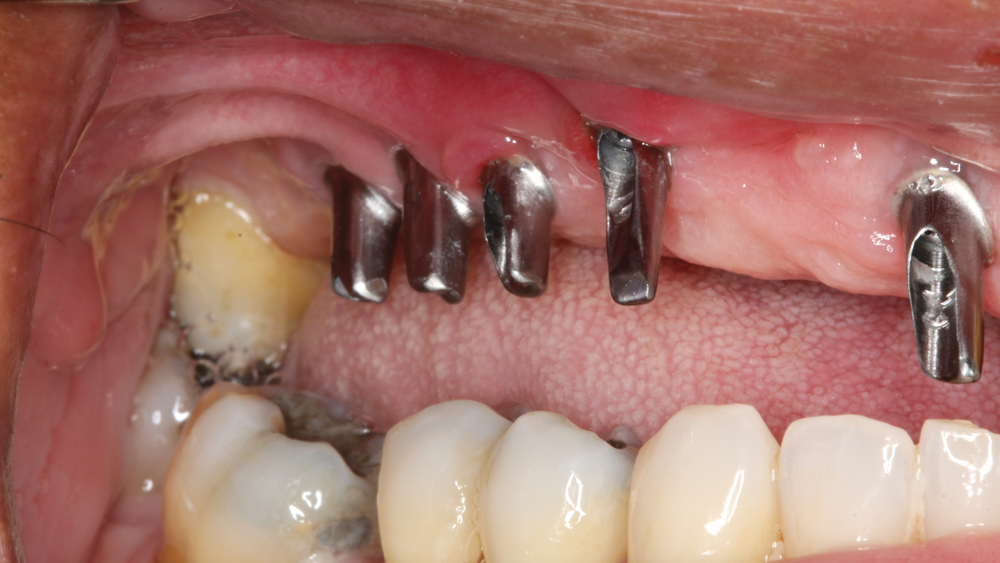

RESTORING THE CASE

Following integration of the implants for approximately four months, a final impression was made using Hahn Open-Tray Impression Copings (Glidewell Direct). The laboratory created a master cast and fabricated Inclusive® Titanium Custom Abutments for a cementable, implant-supported prosthesis. A screw-retained prosthesis was considered for this case, but because of the angulation of the seated implant fixtures, access holes would have exited through the facial aspect of the final prosthesis. Note that the patient is able to maintain the health of the tissue in the area of the restoration with a water pick, and the BruxZir Solid Zirconia material resists bacterial adhesion.

RESTORATIVE TECHNIQUES FOR ESTHETICS AND OCCLUSION